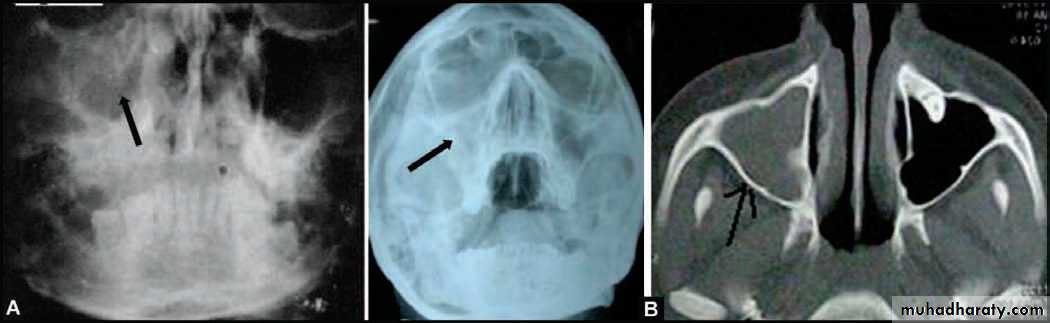

(A) PA view of Water’s position showing haziness of the (R) maxillary sinus, following extraction of upper right first molar 3 months back. Chronic maxillary sinusitis with oroantral fistula (B) PA view Water’s position and CT scan picture of another patient showing complete haziness of (R) maxillary sinus, indicating chronic maxillary sinusitis